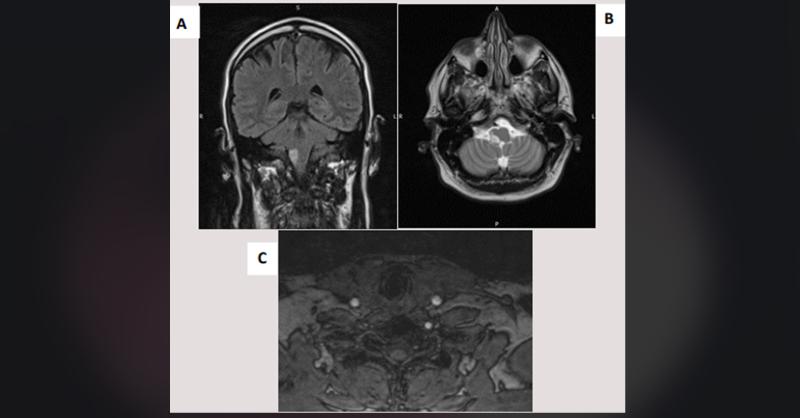

Ischemic stroke is caused by hemodynamic insufficiency in parts of the brain fed by the vertebral artery, which can be caused by direct stenosis of the lumen or thromboembolism (1). Vertebral artery dissection (VAD) is a rare cause of stroke, accounting for about 2% of all ischaemic strokes, although it is a significant cause of stroke in young pat

Delayed Diagnosis of Traumatic Vertebral Artery Dissection after La Tomatina Festival